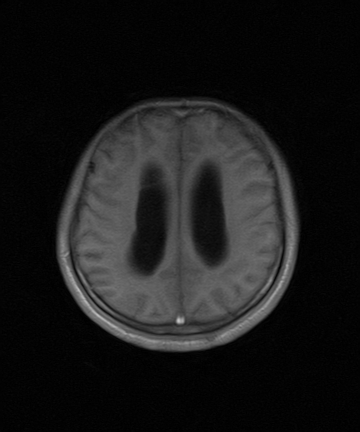

标题: MRI2064:少见病例。男性52,视力下降多年。 [打印本页]

标题: MRI2064:少见病例。男性52,视力下降多年。

四脑室区见混杂信号占位影,脑室系统扩张明显,临近结构显著受压称位,患者52岁,多考虑室管膜瘤可能性大

考虑第四脑室室管膜瘤并阻塞性脑积水。

考虑第四脑室室管膜瘤并梗阻性脑积水;部分性空蝶鞍;左侧上颌窦粘膜下囊肿。